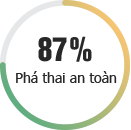

BỆNH PHỤ KHOA

Những bệnh lý ở “vùng kín” có thể đe dọa nghiêm trọng đến tâm lý, đời sống và đặc biệt là sức khỏe sinh sản của người phụ nữ. Đừng bao giờ chủ quan với các bệnh lý phụ khoa mà hãy khám và chữa bệnh kịp thời tại Phòng khám Đa khoa Quốc tế HN